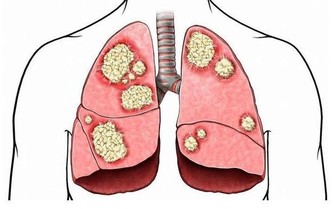

1、胸悶氣短: 一些業主在搬進新家後常常感覺到胸悶氣短、呼吸不暢,但去醫院檢查又沒有發現任何心肺問題,這種情況很有可能是甲醛中毒引起的。胸悶是甲醛中毒常見症狀之一,一般在輕度或中度中毒時出現。所以,如果時常在家中感到胸悶,首先應去醫院排除心臟問題,然後再確定是否是甲醛超標造成的。

2、呼吸系統刺激: 回家開門的一瞬間,家的溫馨氣息就會撲面而來,但新家不是這樣,新業主每次回家聞到的第一縷空氣往往伴隨刺鼻的化學品氣味,怎麼會感受到溫馨呢?這種裝修特有的刺鼻氣體的主要有害成分就是甲醛,多數家庭可在通風一個月時間明顯減輕(注意減輕並不等於消除),但如果通風一個月還沒有改觀,那就應該考慮治理室內空氣污染了。